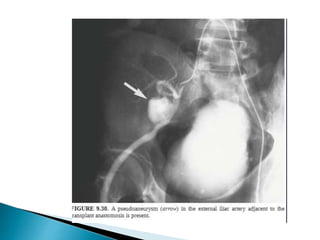

 ESRD , usually undergo biopsy  AVF/pseudo-

aneurysm.

 USG/CT/MRI/Radionuclide studies. Specific imaging – Voiding Cystourethrography.  Evaluation of vessels is by NECT  Assess the degree of calcification = Degree of difficulty in performing the anastomosis.  ESRD , usually undergo biopsy  AVF/pseudo- aneurysm.